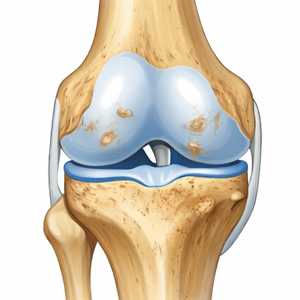

Arthrose wird in die Stadien I bis IV untergliedert

Stadium I

Leicht

Knorpelverlust

Stadium II

Mäßige Arthrose

Gelenkspaltverengung